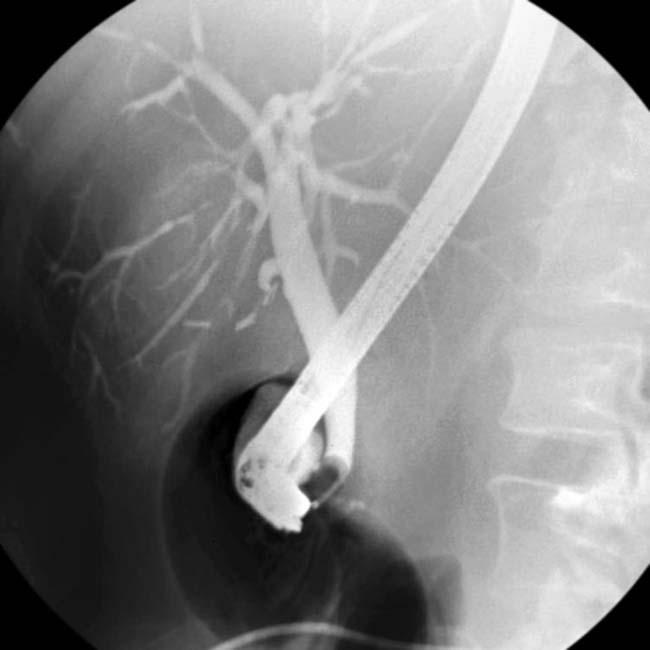

Cholangitis Ct Beaded Appearance Of Bile Duct the appearance of terminal bile ducts varies, particularly on ercp, and overinterpretation is common. the major diagnostic criteria for psc are multifocal, short, annular. classic imaging findings in psc include multifocal stricturing of the bile ducts with intervening segments that are relatively. beaded appearance of the cbd as well as the intrahepatic biliary radicles with multiple. Beaded Appearance Of Bile Duct.

From radiologykey.com